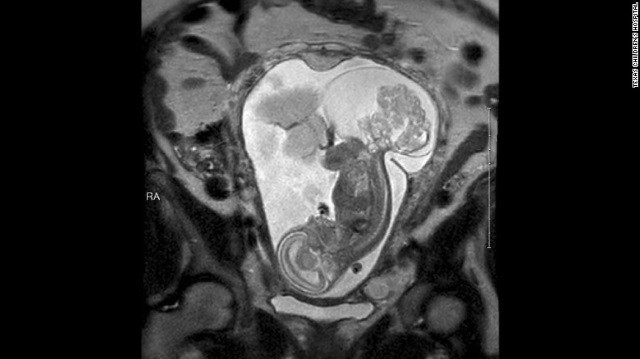

Сакрококцигеалният тератом е тумор на опашната кост, който се развива още преди раждането на бебето. Това е най-често срещаното туморно образувание при новородените според д-р Дарел Кас от Центъра по детски болести в Тексас. Появява се при едно на 35 000 деца, повечето от които – момичета.

В някои случаи туморът може да бъде отстранен след раждането, твърдят лекарите, но обясняват, че той може сериозно да увреди плода заради проблеми с кръвообръщението.

„Туморът расте, като „изсмуква” кръв от бебето (…) Често сърцето не може да издържи и детето умира”, разказва д-р Кас.

За да отстранят тумора, лекарите изваждат плода от утробата на майката. Това се оказва изключително опасно, тъй като всички околоплодни течности изтичат.

В продължение на цели пет часа докторите работят внимателно, стараейки се и плодът, и родилката да останат невредими. Операцията се оказва много сложна и тежка – сърцето на бебето почти спира, но специалистите не се отказват и в крайна сметка я завършват успешно.